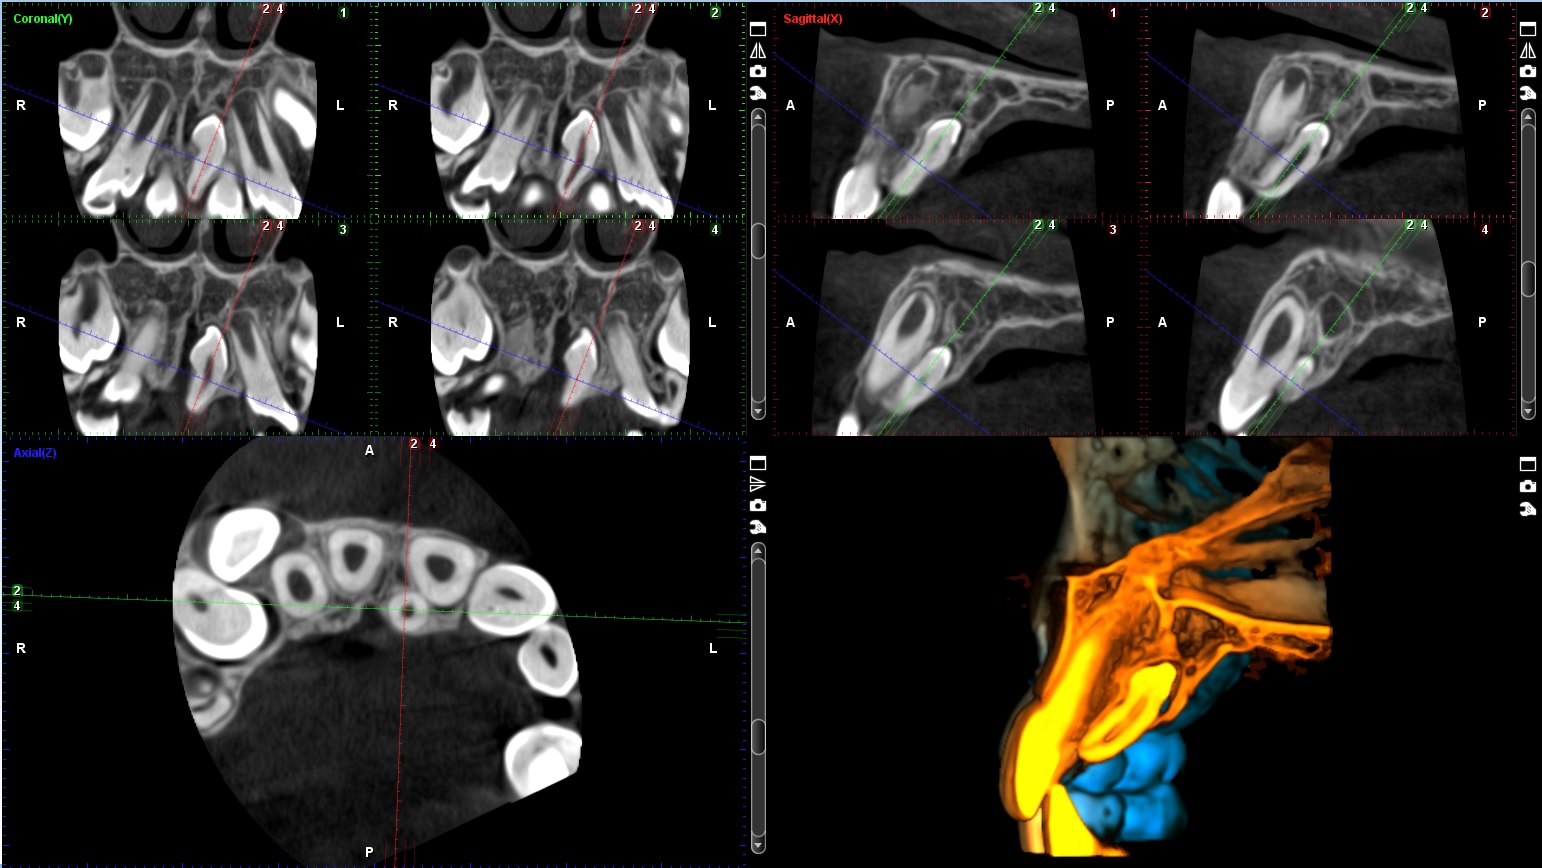

3D snimanje zuba, poznato kao konusni snimak (Cone Beam Computed Tomography – CBCT), pruža detaljan trodimenzionalni prikaz zuba, vilice i okolnih struktura. Ovaj napredni rendgenski postupak omogućava visoku preciznost u dijagnostici i planiranju tretmana, kao što su implantati, ortodontski aparati, lečenje korena i hirurške intervencije. Korišćenjem Planmeca aparata, CBCT omogućava detaljnu analizu čak i najmanjih struktura, što pomaže stomatolozima da donesu tačne i efikasne odluke za svaki specifičan slučaj.

Količina zračenja tokom 3D snimanja zavisi od veličine skenirane oblasti i veličine vokselâ (voxel size). Za aparat Planmeca ProMax 3D Mid, koji je poznat po visokoj preciznosti uz smanjeno zračenje, prosečna doza zračenja za 3D snimanje zuba je približno 10–20 mikrosiverta (µSv). Ovo je značajno niže u poređenju sa tradicionalnim CT snimanjima, koja mogu imati doze zračenja od 100–200 µSv.

3D snimci kao na sajtu.

3D - SNIMCI